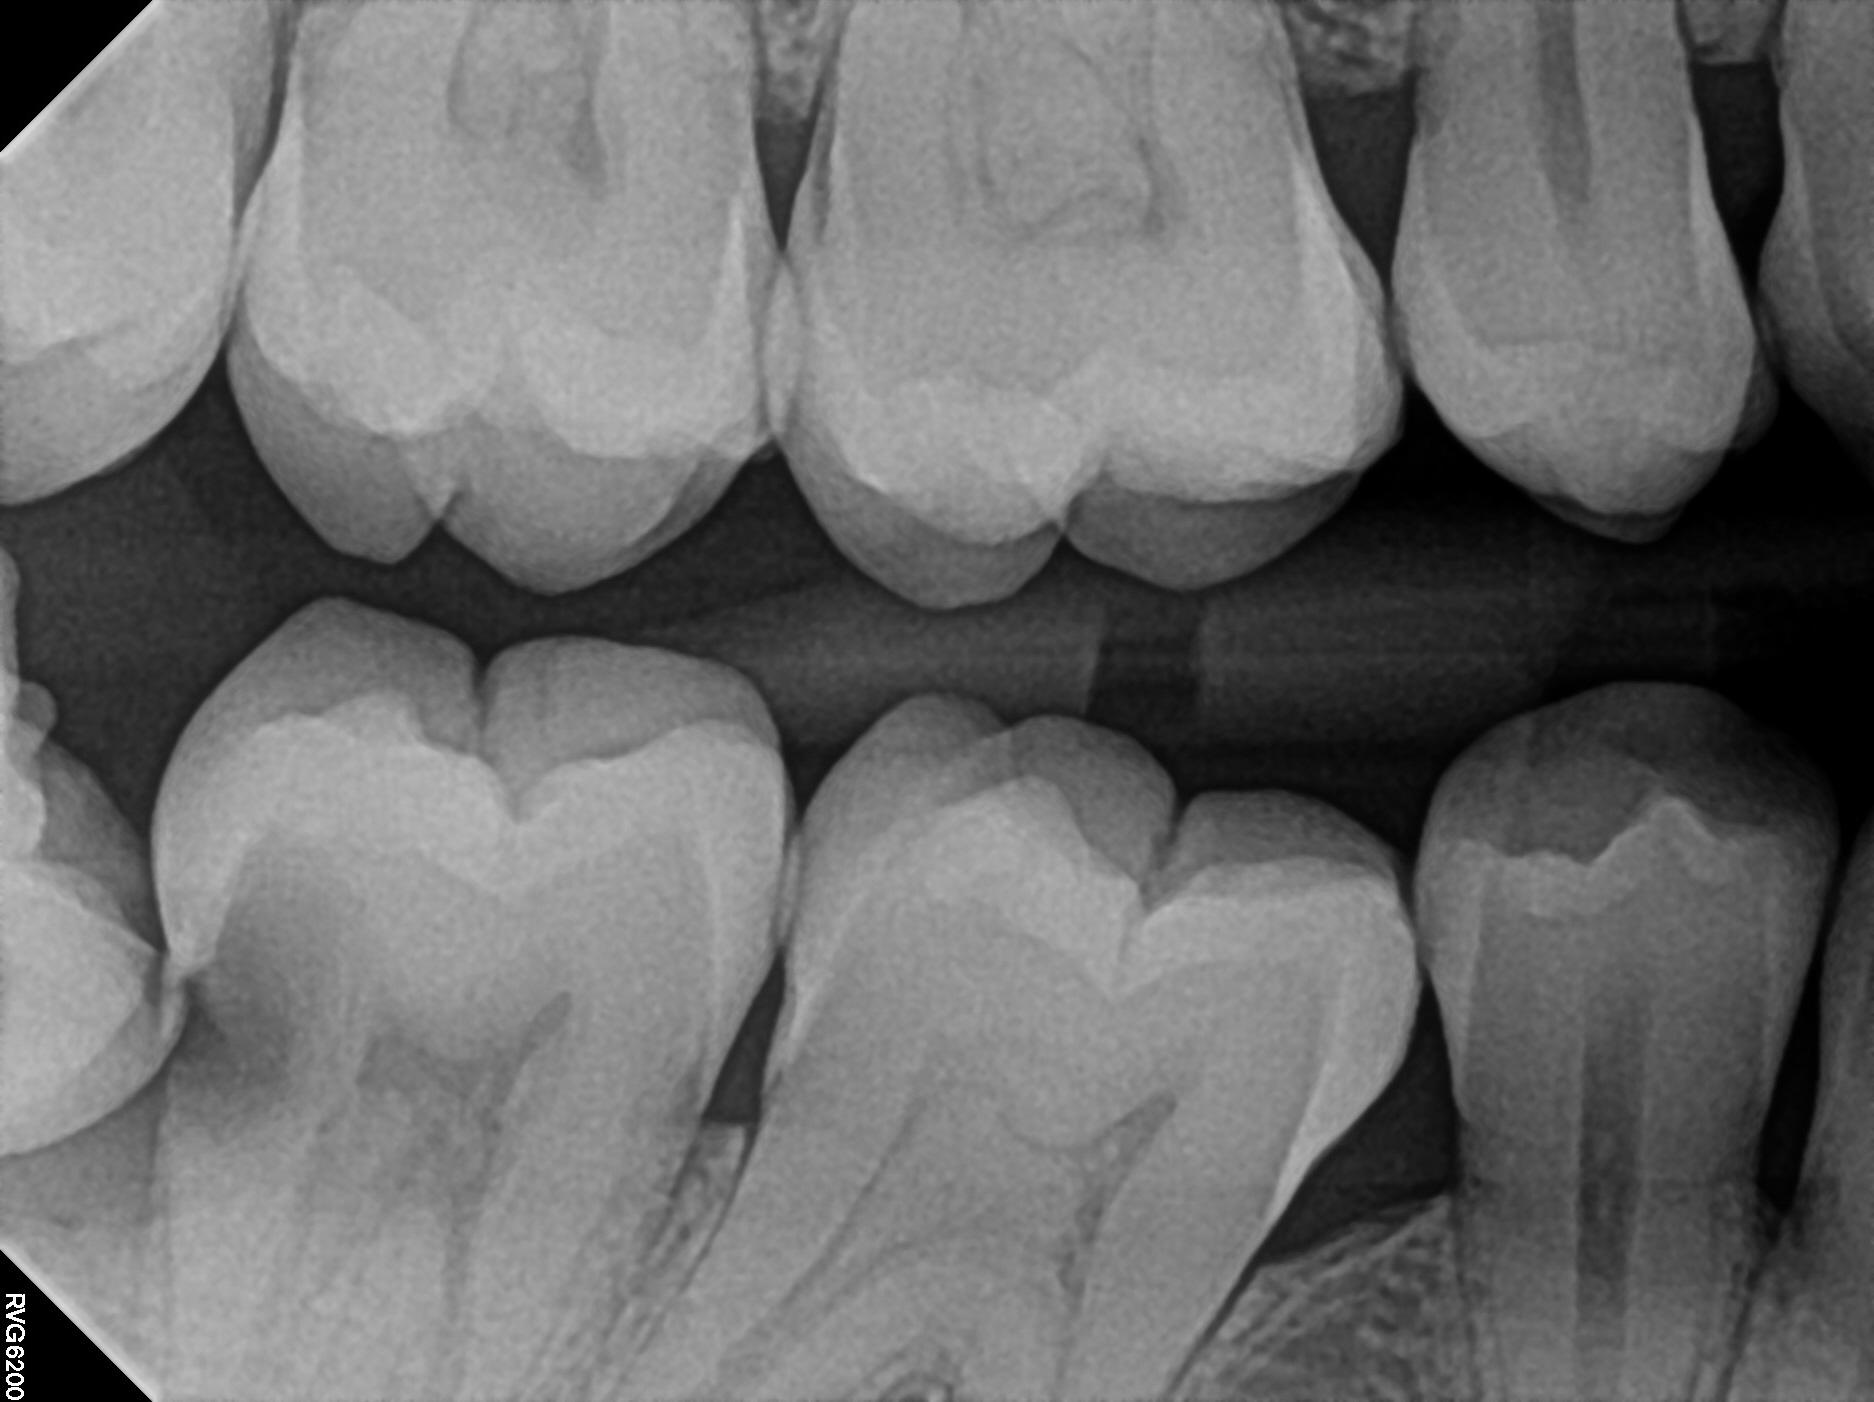

Wisdom Teeth Removal In Richmond: Why Delaying Extraction Can Damage Healthy Teeth admin 03/10/2026 Wisdom teeth are something most people hear about in their late teens or early twenties, often with the assumption that Read More